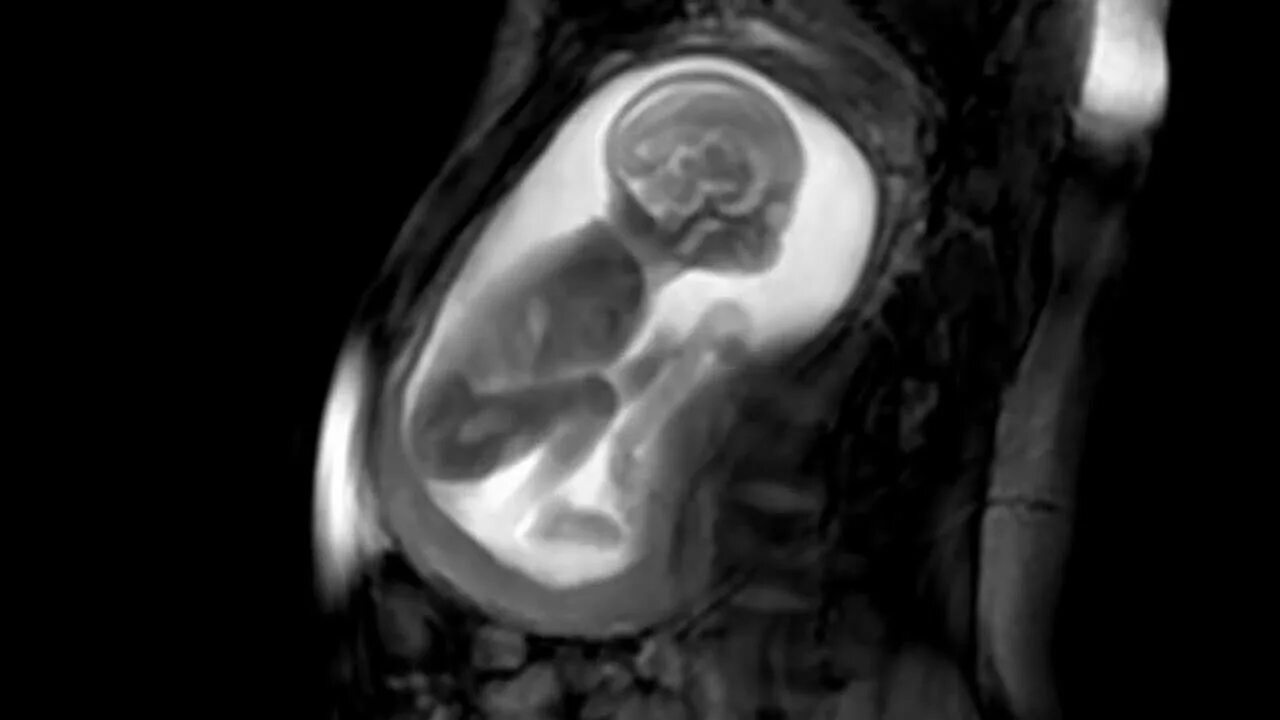

Мрт беременной